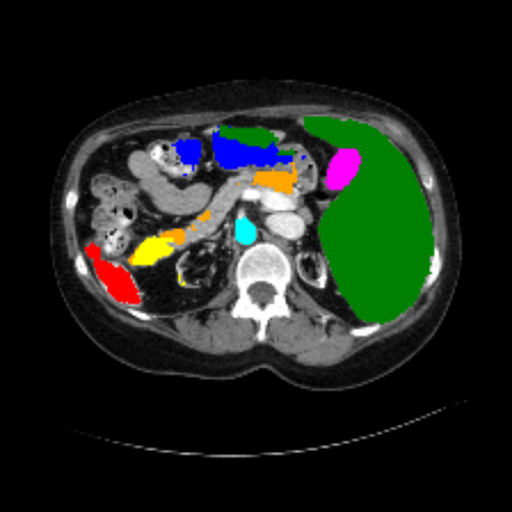

Figure 3 presents a qualitative comparison of segmentation performance on examples from the Synapse, BTCV, ACDC, and ISIC17 datasets. The first two examples (from Synapse) highlight variations in segmentation performance among U-Net, TransUnet, Mamba-Unet, and Swin-Unet. While Swin-Unet performs well in the first example, its performance decreases in the second example, particularly in segmenting the organ highlighted in blue. Additionally, it misclassifies background regions as the class highlighted in orange. In contrast, our approach demonstrates high robustness in segmenting all classes accurately and aligning well with the ground truth masks.

Refer to caption Refer to caption Refer to caption Refer to caption Refer to caption Refer to caption Refer to caption

Slice GT Unet TransUnet Mamba-Unet Swin-UMamba MambaCAFU-V1

Figure 3: Visual comparison of segmentation examples from Synapse (first two examples), BTCV (3-4 examples), ACDC (5th example) and ISIC17 (last example). Columns: input slice, ground truth, Unet, TransUnet, Mamba-Unet, Swin-UMamba, and MambaCAFU-V1.